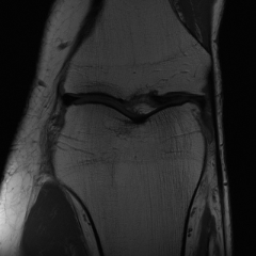

5.3 Out-of-Domain Generalisation

One way to test the generalization capability of the trained X-Diffusion is to test it on a completely different domain from an MRI dataset not seen during training. We report the single-slice results on NYU fastMRI [37, 82], a knee MRI dataset, using the X-Diffusion trained on the BRATS brain MRIs. The results are shown in Figure 9 and Table 2. It shows how successfully X-Diffusion is able to generate knee MRIs from a single image, despite not seeing knees at all in training. To qualitatively assess how realistic our generated 3D volumes were (produced from a single slice), we gave 20 generated examples alongside their real MRI counterparts to an expert orthopaedic surgeon. He was then asked to identify the real example from a given pair. The surgeon identified with certainty only 10 real knee MRIs out of 17, while could not decide on the remaining 3 of the 20 MRI pairs. This further validates the generated out-of-domain MRIs.